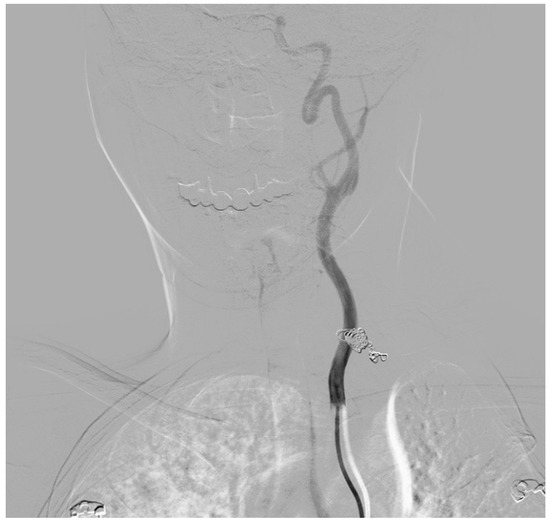

2. Case Presentation

| 3 days after CS | Admission to Centre for Vascular Surgery | Left sided ipsilateral thyrocervical trunk ruptured aneurysm |

| 3 days after CS | Centre for Vascular Surgery | emergency endovascular coiling intervention |